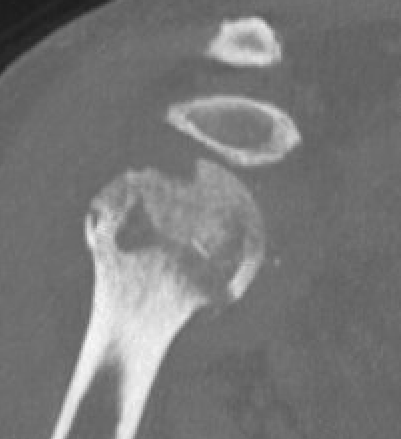

CT

Assess bone stock / glenoid bone loss / Hill Sachs lesions

Chronic shoulder dislocation with large Hill Sachs and minimal glenoid deficiency

Chronic shoulder dislocation with large Hill Sachs and significant glenoid deficiency